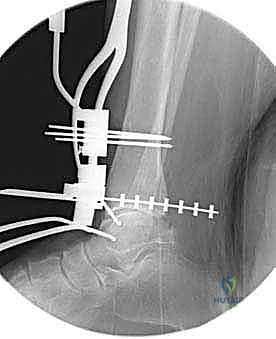

تعتمد دقة الجراحة على المحاذاة الصحيحة. يتم استخدام أجهزة توجيه متطورة (Jigs) تثبت على عظمة الساق باستخدام دبابيس معدنية. يتم التحقق من صحة الزوايا والمحاور باستخدام جهاز الأشعة السينية المباشر داخل غرفة العمليات (C-arm Fluoroscopy). يضمن الدكتور هطيف أن يكون القطع موازياً للأرض تماماً عند وقوف المريض.

5. القطع العظمي الظنبوبي (Tibial Bone Cut)

باستخدام منشار جراحي دقيق التذبذب، يتم إزالة شريحة رقيقة جداً (بضعة مليمترات) من السطح السفلي التالف لعظمة الظنبوب. يتم القطع بحذر شديد لتجنب إصابة الأوتار الخلفية أو الأوعية الدموية.

6. القطع العظمي الكاحلي (Talar Bone Cut)